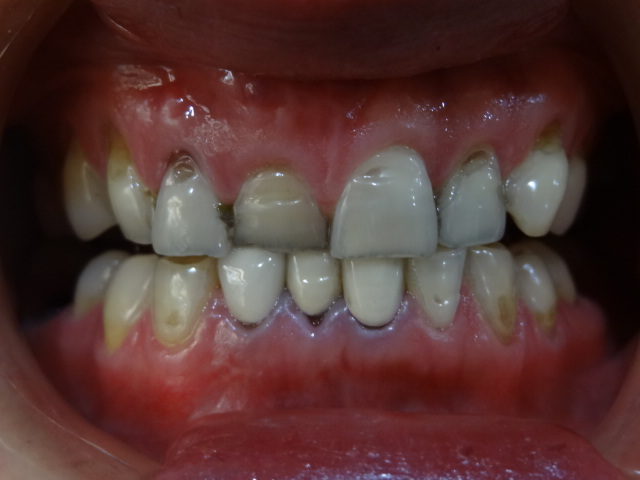

術(shù)前

初中就開始抽煙,我是標(biāo)準(zhǔn)的滿口煙牙,這不過(guò)年要去女朋友家里拜訪,為了給她家人留個(gè)好一點(diǎn)的印象,衣服買了,鞋子也買了,女朋友說(shuō)讓我去把牙齒洗一下,不然都不能大笑,沒(méi)辦法,細(xì)節(jié)也要注意,就去了!

做完超聲波洗牙第二天,牙齒還是有酸酸的感覺(jué),不過(guò)牙齒真的白了很多,看起來(lái)干凈了不少,走在路上我時(shí)不時(shí)傻笑,女朋友以為我傻了,哈哈!